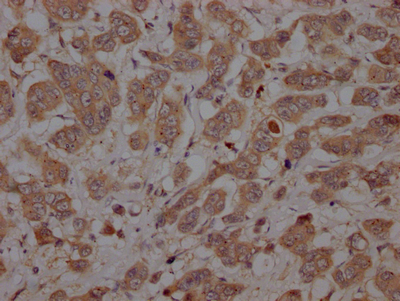

• IHC image of CSB-RA182616A0HU diluted at 1:100 and staining in paraffin-embedded human breast cancer performed on a Leica BondTM system. After dewaxing and hydration, antigen retrieval was mediated by high pressure in a citrate buffer (pH 6.0). Section was blocked with 10% normal goat serum 30min at RT. Then primary antibody (1% BSA) was incubated at 4℃ overnight. The primary is detected by a Goat anti-rabbit IgG polymer labeled by HRP and visualized using 0.05% DAB.